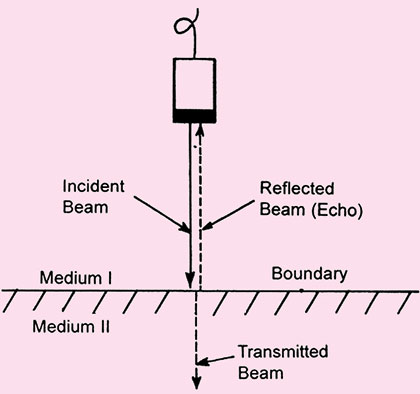

Reflection is the return of incident ultrasound energy as an echo directly back to the transducer when 3interacting with boundary at normal incidence. Reflection occurs at the interface between two dissimilar materials (Figs 1.3A and B).

Angle of incidence The angle of incidence is equal to angle of reflection. These angles are defined relative to a line drawn perpendicular to the surface of interface.

Amount of reflection is determined by angle of incidence. Higher the angle of incidence, less the amount of reflected sound wave.

Fig. 1.3A: Specular echo. The figure represents what happens when an ultrasound beam interacts with an acoustic boundary (i.e. where medium I and medium II have different acoustic impedances). Note that under these circumstances, the beam strikes the boundary at a 90-degree angle. This results in an undeviated transmitted beam and a reflected beam, which is called a specular echo